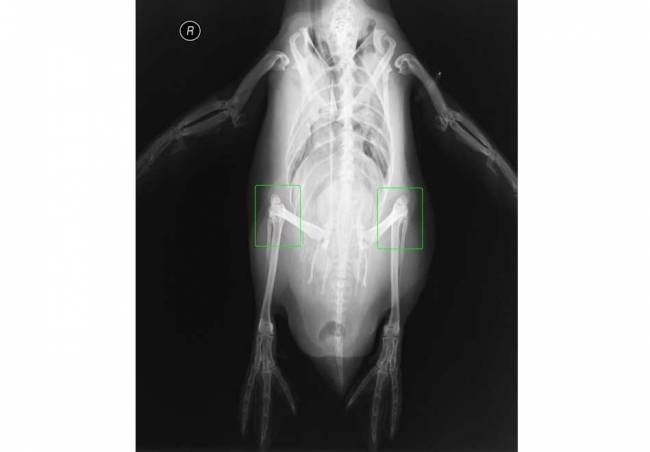

Doğaya Bakışınızı Değiştirecek 15 X-RAY Görüntüsü

Doğaya Bakışınızı Değiştirecek 15 X-RAY Görüntüsü galerisi resim 3

Penguenlerin dizleri var.